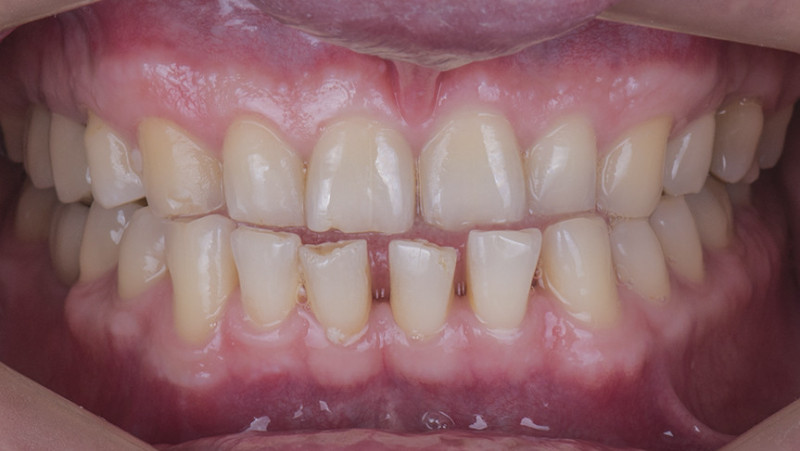

Установка металлокерамической коронки

Провели швейцарскую профгигиену. Перелечили зубы с несостоятельными пломбами и воспалениями. Провели имплантацию. На нижней челюсти провели отбеливание ZOOM. Установили керамические коронки EMAX на верхней челюсти в количестве 14 единиц и на нижней челюсти в области группы жевательных зубов.